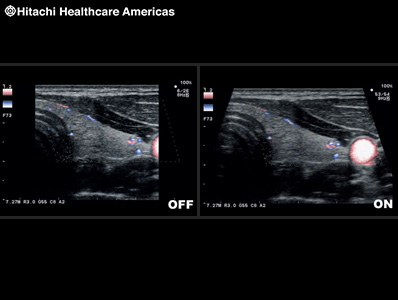

To improve understanding of blood flow information, Fujifilm Healthcare offers harmonics enhanced imaging specifically designed for use with contrast agents. The low MI contrast imaging obtained improves signal-to-noise ratio.

* In the USA, contrast-enhanced ultrasound has not been market cleared by the FDA for all imaging applications.